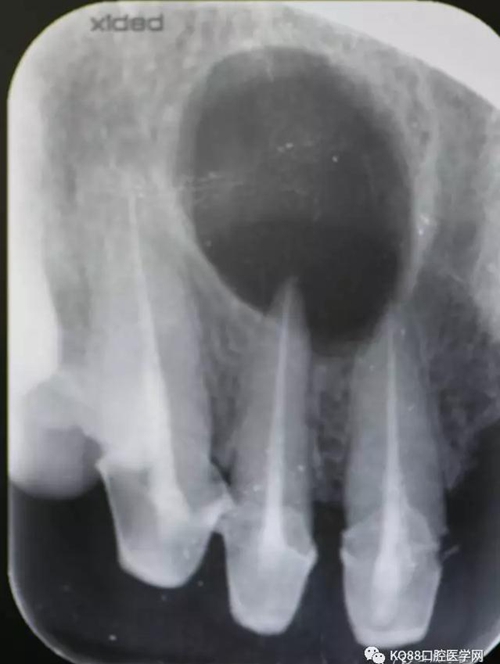

圖2.拆冠、重新根管治療11和12.